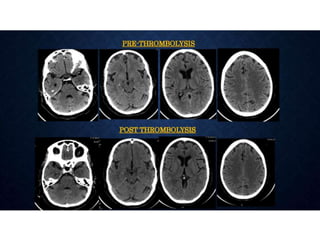

ACUTE STROKE IMAGINGPROTOCOL • When acute stroke patients present within 6 hours of the onset of symptoms - un-enhanced CT or with conventional/MR imaging. • Hemorrhage at unenhanced CT or >1/3 MCA territory - not treated with thrombolytic drugs. • Ischemia of < 1/3 MCA territory, those who present <3 hours after the onset of acute stroke - intravenous thrombolytic drugs • 3–6 hours after the onset of symptoms - CT angiography and CT perfusion imaging to assess the intracranial and neck vessels and detect any penumbra. • Intraarterial therapy is usually considered for patients in whom a penumbra is seen. • Patients in whom no penumbra is seen are not usually treated with thrombolytic drugs

CTP IN STROKE •• Stroke is a leading cause of mortality and morbidity in the developed world. • • The goals of an imaging evaluation are • I. to establish a diagnosis as early as possible • II. to obtain accurate information about the intracranial vasculature • III. to identify critically ischemic or irreversibly infarcted tissue (“core”) and to identify severely ischemic but potentially salvageable tissue (“penumbra”). • This information can guide triage and management in acute stroke.